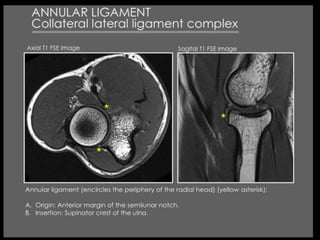

Presentation1, musculoskeletal anatomy.